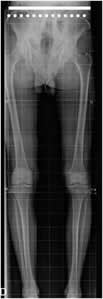

Eje mecánico:

Corresponde a la línea que se origina en el centro de la cabeza femoral, hasta la mitad de la articulación del tobillo, situada en el centro de la tróclea astragalina. (1). Normalmente debe cruzar por el centro de la rodilla, entre las espinas tibiales o a una distancia medial o lateral, menor de 10 mm. (1, 3). Este eje forma un ángulo de 3º con la vertical y de 6º con el eje del fémur. (1, 3). (Fig 96 y 97 A).

Las líneas tangenciales a las superficies articulares proximal y distal de la tibia son paralelas o forman un ángulo con eje medial, menor de 5º. (1). (Fig 97 B).

Fig 96. Eje mecánico.

Rx AP. Línea entre el centro de la cabeza femoral y el centro de la tróclea astragalina, que cruza las espinas tibiales.

Fig 97 A. Eje mecánico.

A y B: Rx AP. El eje mecánico forma ángulo de 3º con la vertical en A y de 6º con el eje del fémur en B.

Fig 97 B. Líneas tangenciales.

Rx AP. Relación entre las superficies articulares tibiales superior e inferior, con ángulo de vértice medial.